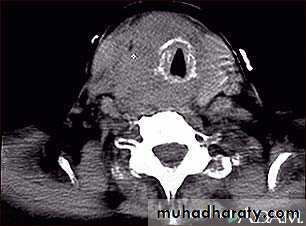

D-Imaging study1-plan X ray of the neck: to evaluate the trachea, retrosternal extension and cervical spine . 2-Ultrasound: distinguishing solid from cystic masses, information about size and multicentricity, assess cervical lymph nodes and guides for FNAC.

3-CT scan and MRI: assessment of known malignancy, extent of retrosternal and occasionally recurrent

Goitres.